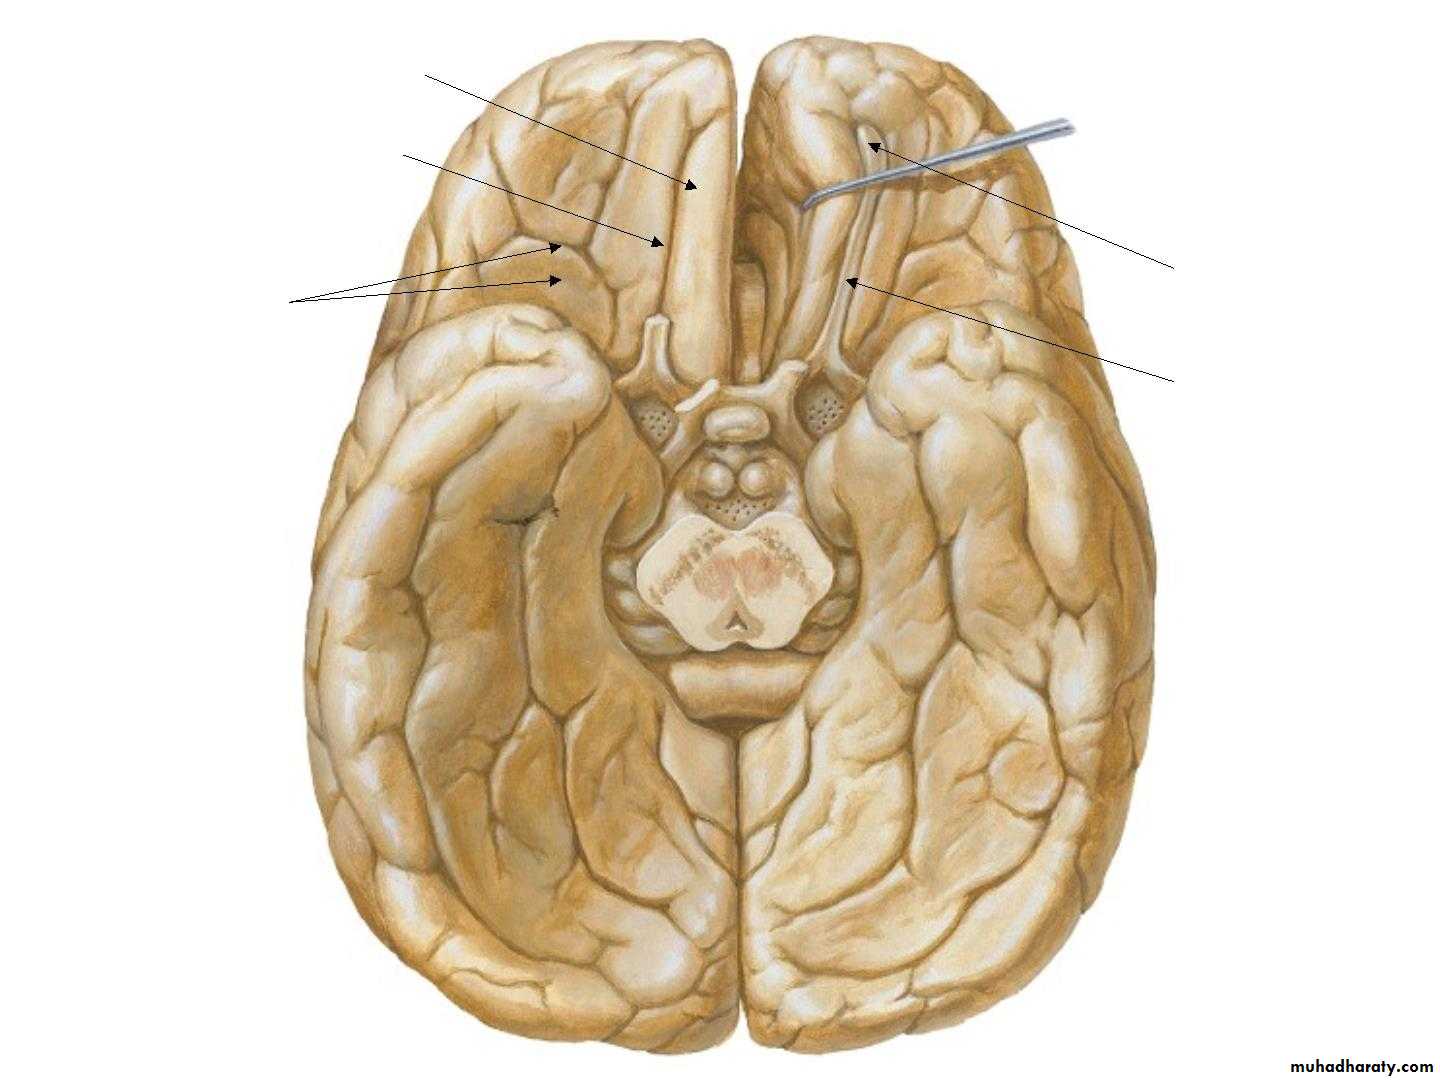

• 3. Inferior surface

• Gyrus rectus

• Olfactory sulcus• Olfactory

• bulb

• Olfactory

• tract ,

• Orbital gyri

• & Sulci

• Collateral sulcus

• Uncus• Occipitotemporal

• sulcus